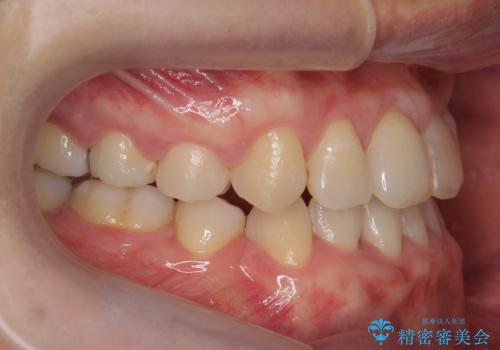

受け口 絶対に顎の手術はしたくない

- 受け口を主訴に来院。

下あごが大きく、顎の手術を含めた矯正をおすすめしましたが、手術は怖いので絶対にしたくないとのことでした。

歯並びのみを治す矯正は難しく、長期にわたる治療になるとご説明しました。

かみしめもあり、骨も固く、歯根も長いためなかなか歯が動かず、患者様も治療する側も忍耐を要する長期戦となりました。